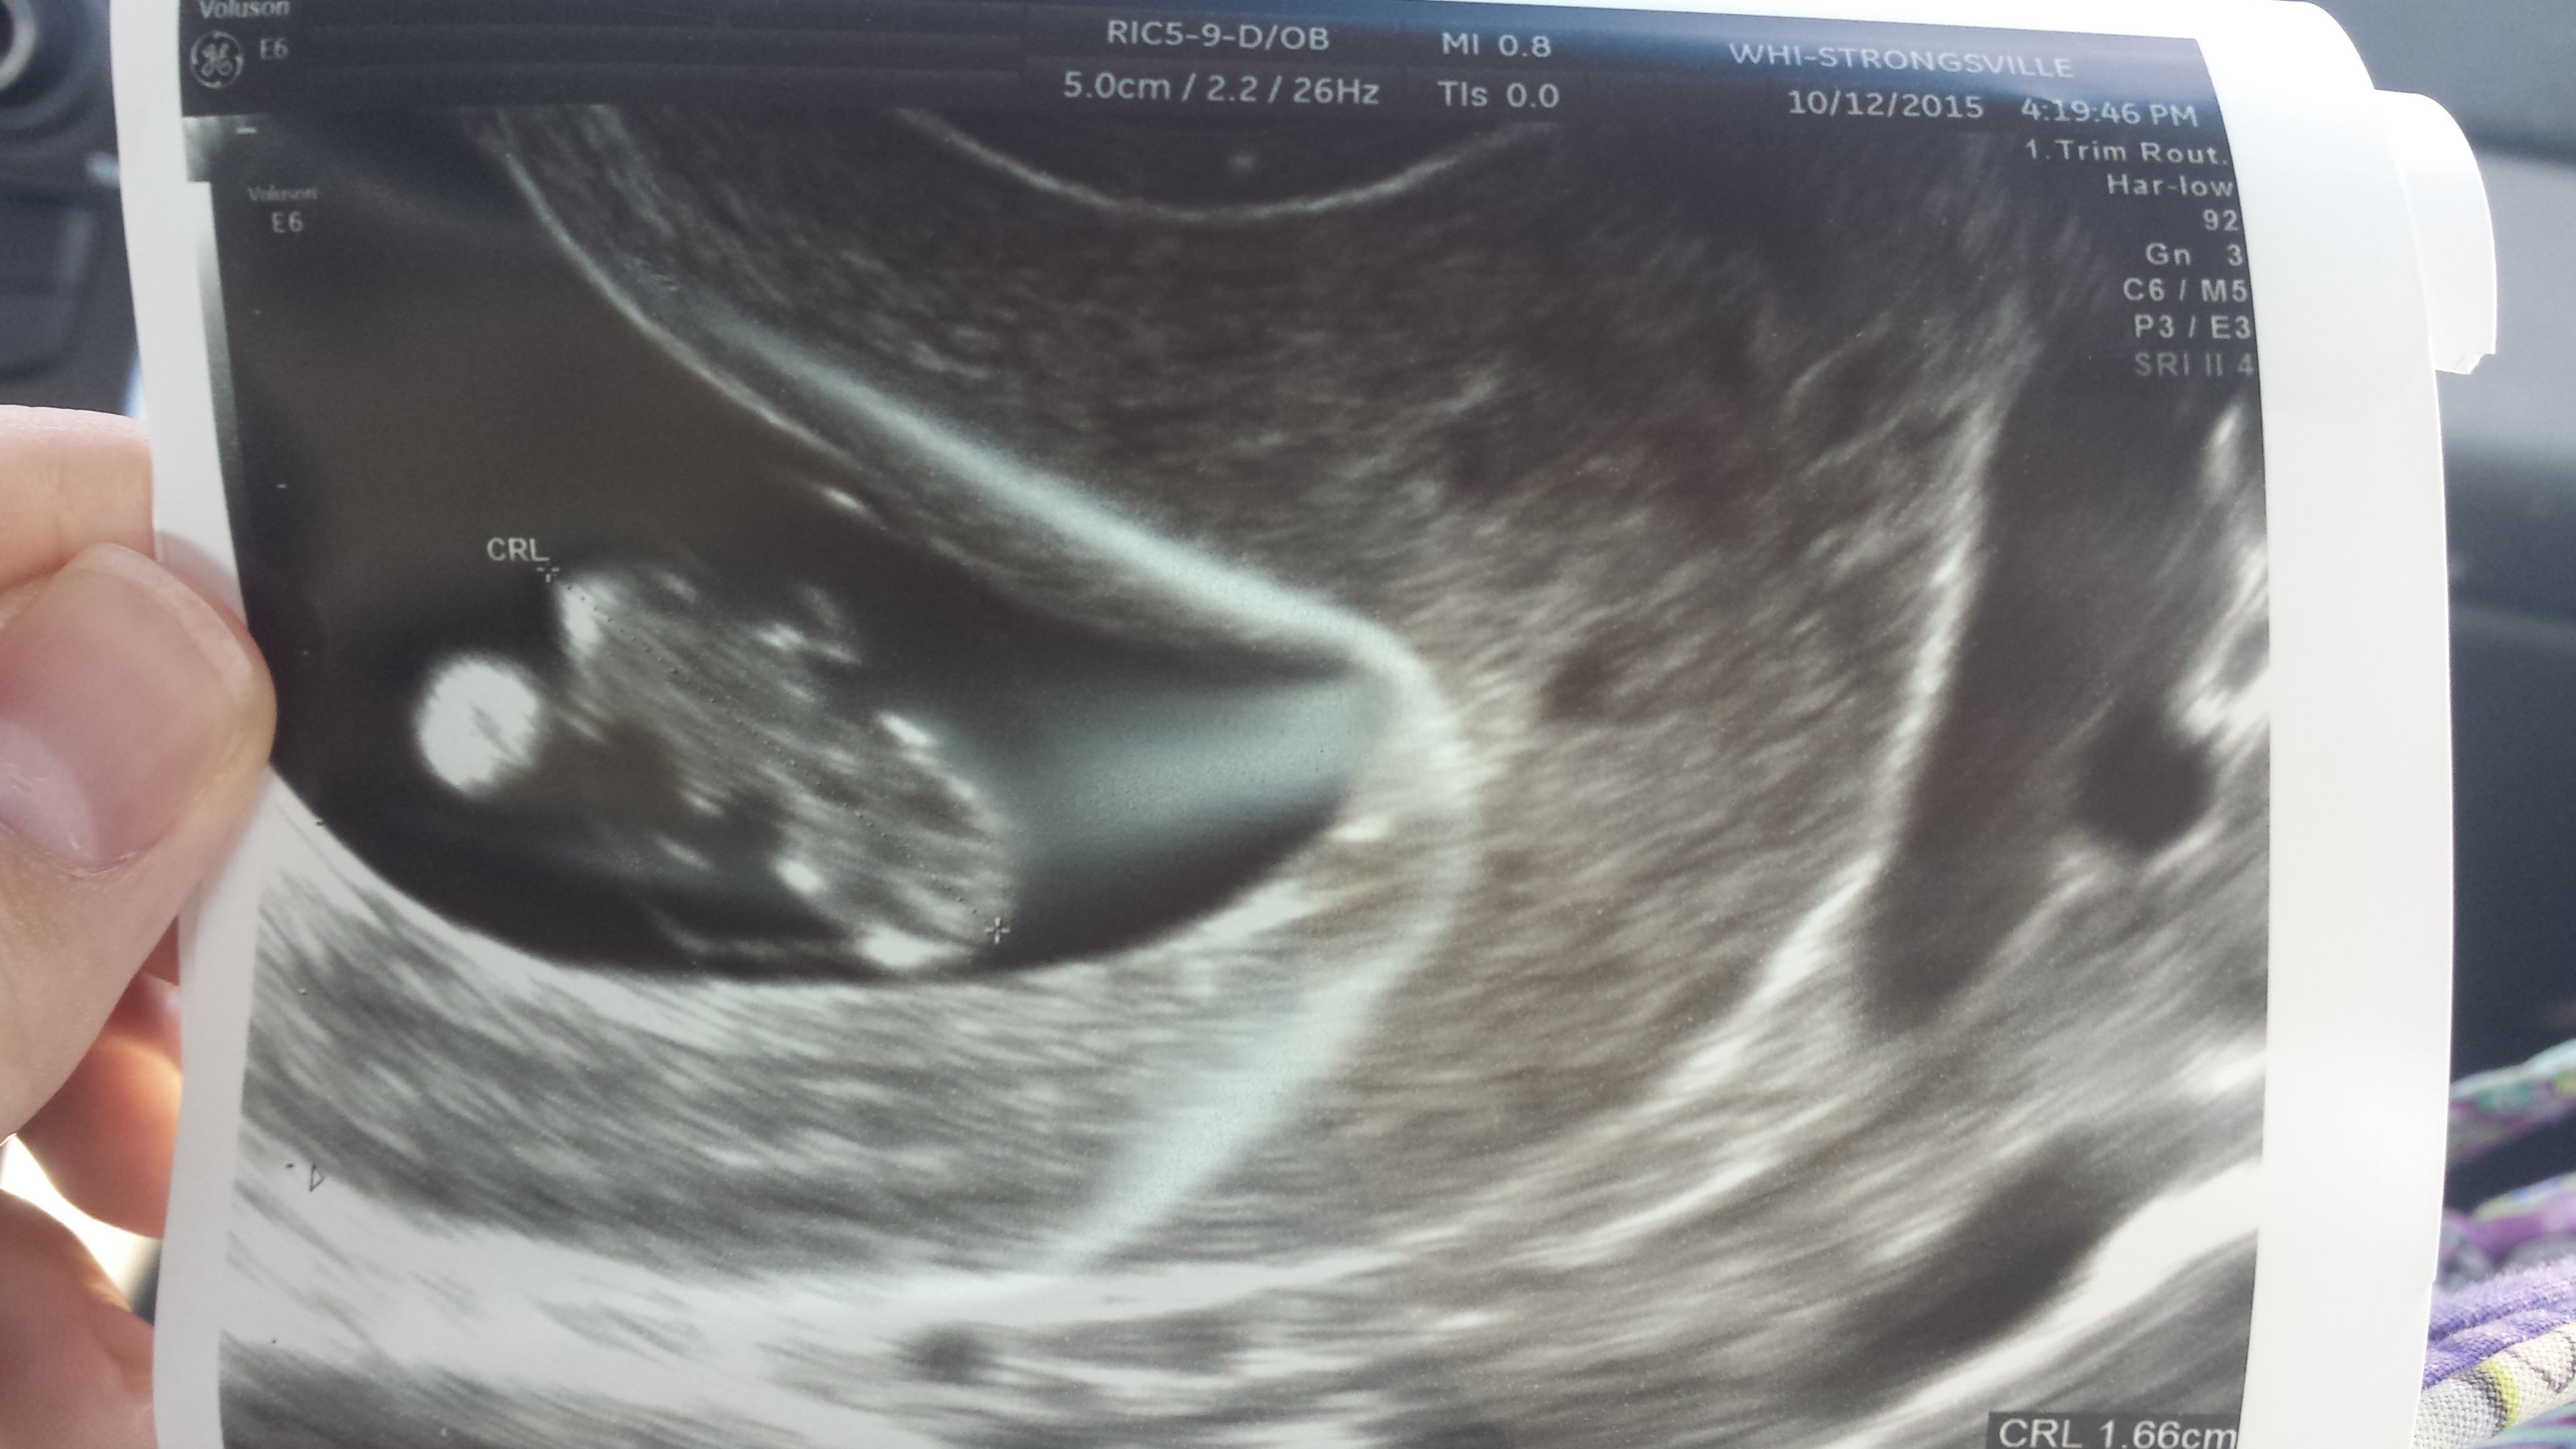

New discussion button is missing for me on my laptop. I had my first appt today expecting to be 8 weeks based on LMP. They did a transvaginal ultrasound because they were worried about a possible cyst and the sac was measuring at only 5w4d. You couldn't see anything in it yet. Based on when I think I ovulated, this would make sense... my cycles are usually long... but that didn't stop me from bursting into tears. Neither the tech or the doctor were worried and they want me to come back in 2 weeks for another ultrasound, but I'm freaking out. Is 5w4d just too early to see anything? Did anyone else have their EDD completely wrong when they went for an ultrasound?

If your cycles are unusually long, you shouldn't have based how far along you thought you'd be on your LMP. So, if you are only 5w4d, seeing the gestational sac sounds fine. I only saw the gestational sac at 5w2d, saw the yolk sac four days after that and saw the heartbeat at my 7w appointment. I know it's really hard (especially when so many other women see things a lot earlier), but try to remain calm and think positively.